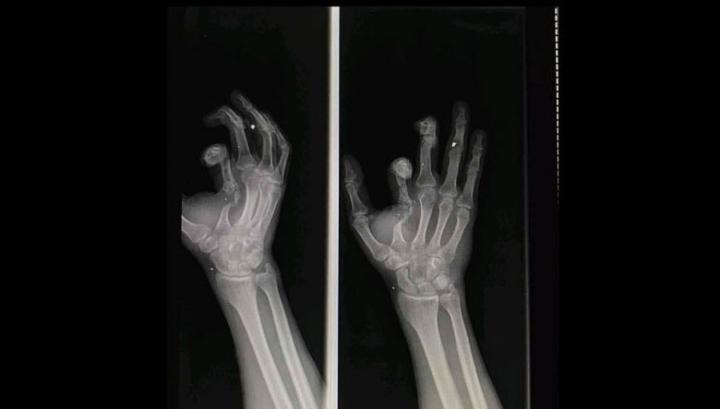

«Սիրելի Հայրենակիցներ, այսօր ինձ զրկեցին հաշմանդամության կարգից և դա արեցին նիկոլ փաշինյանի հրամանով։  Ես շատ ուրախ կլինեի, որ իրապես հաշմանդամ չլինեի և թքած ունեմ դրանց տված 60.000 դրամի վրա, բայց իրականում իմ Ձեռքերը կոտրված են և ես իմ ռենտգենի լուսանկարները Ձեզ եմ ներկայացնում, երկու ձեռքս էլ ջարդված է, երկաթ է դրված և դա պարզ երևում է ռենտգենով։